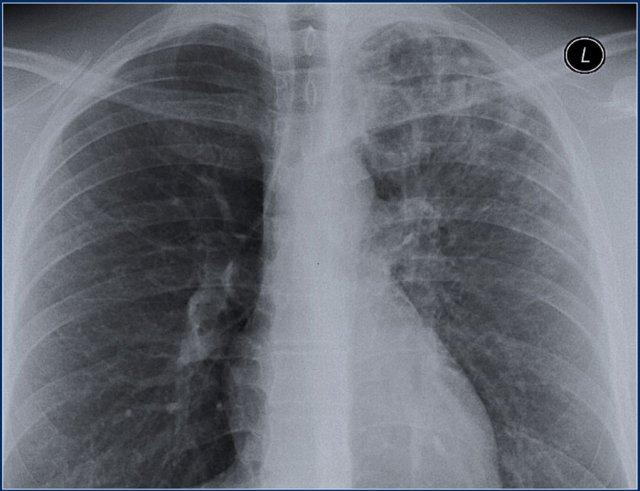

Bệnh nhân này nhập viện lần đầu với phim X quang ngực bên trái.

Hãy quan sát kỹ các hình ảnh trước.

Các dấu hiệu bao gồm:

- Các đám mờ bờ không rõ lan tỏa, có thể là các vùng đông đặc nhỏ.

- Hang ở thùy trên phổi phải.

Có thể nhận định đây là tái hoạt của lao tiềm ẩn.

Cấy đờm dương tính với vi khuẩn lao.

Phim X quang ngực chụp vài năm sau (bên phải) cho thấy:

- Xẹp thùy trên phổi phải

- Lệch khí quản

- Xơ hóa và tạo hang ở phần còn lại của thùy trên

- Xơ hóa tối thiểu và tạo hang ở thùy trên phổi trái.

Điều này được đánh giá rõ hơn trên CT.

Cùng bệnh nhân

Lưu ý hình ảnh tạo hang, đặc biệt ở phổi phải.

Ở thùy trên phổi trái, có thể có giãn phế quản do co kéo (traction-bronchiectasis) liên quan đến xơ hóa.